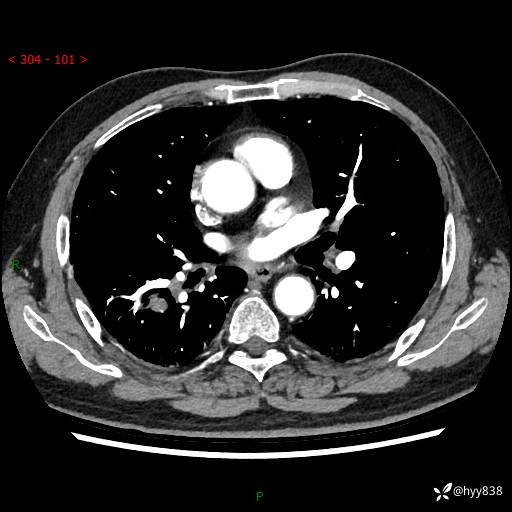

71岁/男,咳嗽伴气促半月。一年前肺手术史,又见两个结节,穿刺结果意外---结果公布~

【现病史】:患者半月前无明显诱因出现咳嗽、咳痰,为白色粘痰,无明显加重与缓解因素,伴气促,无发热,无大量脓痰,无胸痛、咯血,无哮鸣音,到我院就诊,胸部CT示右肺结节增大,并口服药物治疗无明显好转,具体用药不详,为求进一步治疗随来我院,经门诊以“孤立性肺结节”收入我科。 病程中患者精神、饮食可,睡眠不佳,大小便正常,体力下降,体重未见明显下降。

[既往史]:2022-06于当地第一人民医院确诊慢阻肺,现规律使用杰润(1次/日);2023-04-06于当地市第一人民医院行胸腔镜右肺上叶楔形切除术+右肺上叶切除术+淋巴结清扫术+胸膜黏连松解术,确诊为右肺鳞癌 pT2aN0M0 Ib期

【检查】:胸部CT平扫+增强